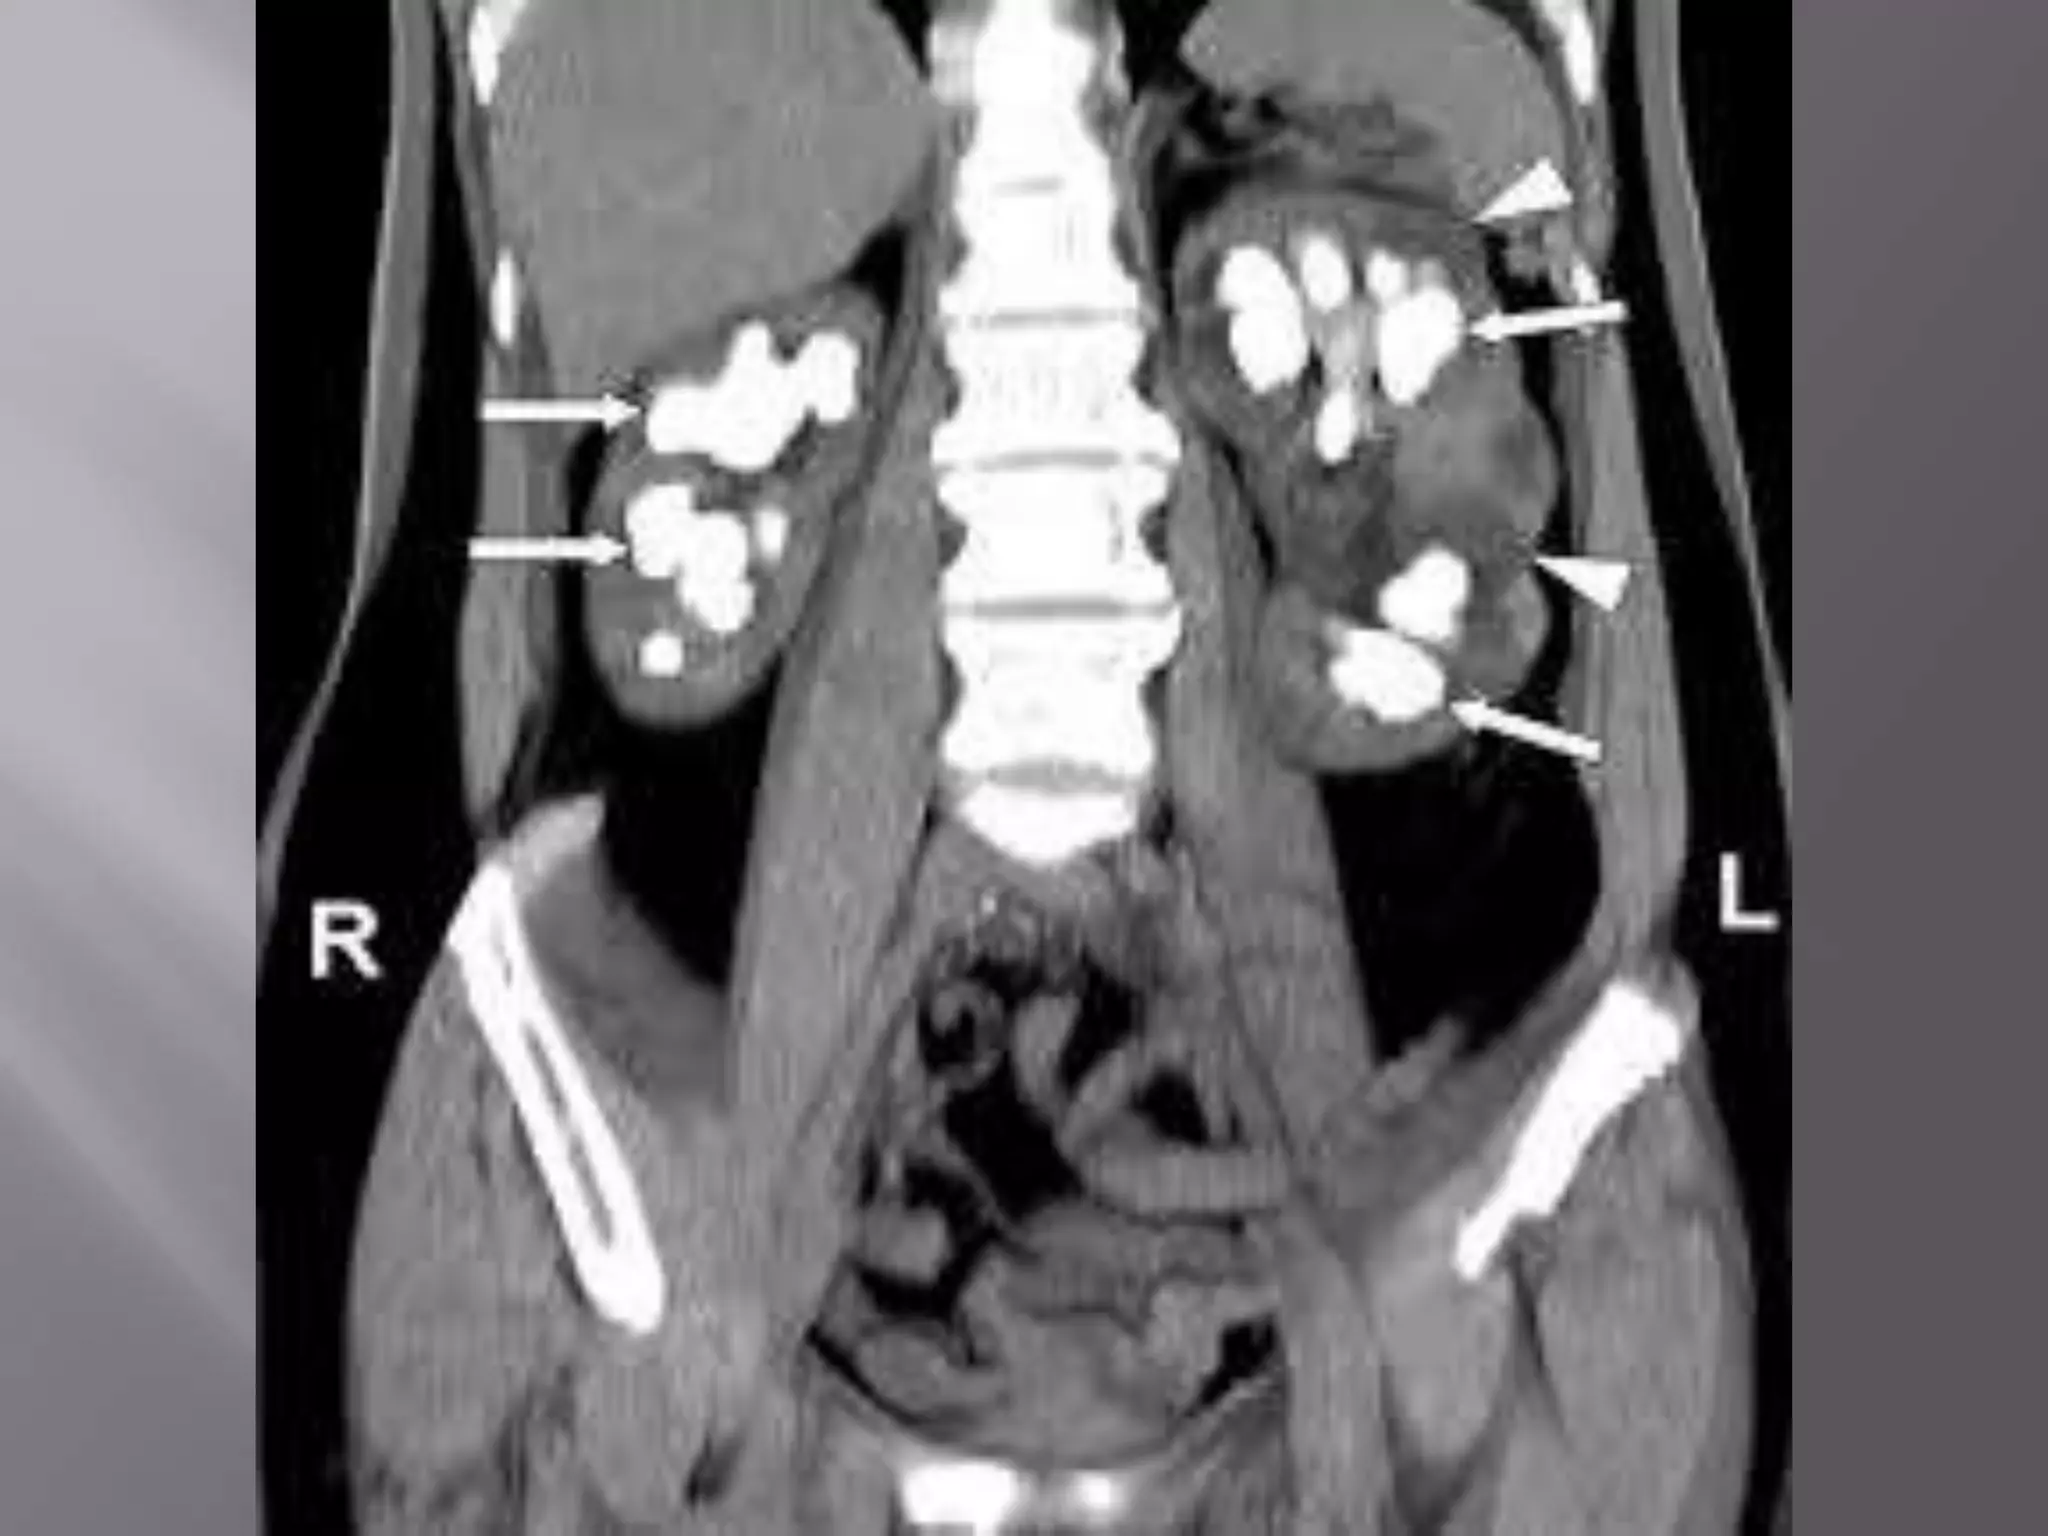

 Ct scan – imaging study of choice.

 noncontrast CT scanning followed by

intravenous contrast CT scanning is obtained

most often in the evaluation of urinary stones.

 CT scans also display the adjacent structures

and may aid in selecting the safest

percutaneous tract to access the renal collecting

system

 Delineates better renal & p-c system anatomy ,

renal excretion of dye , surrounding structure,

parenchymal thickness , hydronephrosis , HU

value